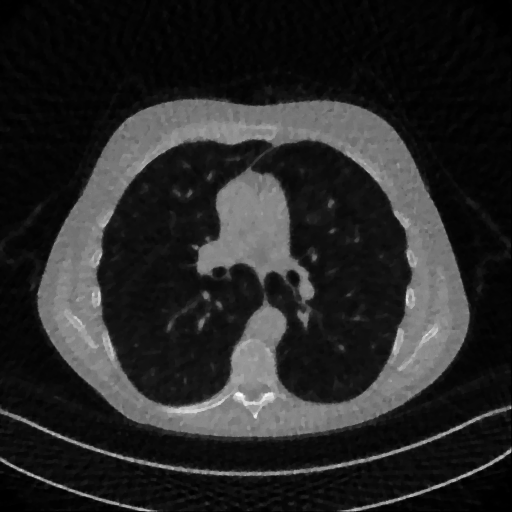

Here we present the results of RISING applied to the Mayo data set introduced in paragraph 4.1. As previously mentioned, we consider two sparse-view CT geometries, namely and . In Figure 4 we report the results for the protocol, achieved on one image of our test set. The top-left image represents the reconstruction. Even if only a small number of iterations are performed, the main structures of the abdomen are visible; however, the image is still blurry. In the image, shown in the upper-right corner, we notice that the TV regularizer has acted to totally eliminate the artifacts and noise, improving the uniformity of the image in the inner structures. When compared to the ground-truth solution in Figure 2, the contours of the details in appear slightly jagged, differently from where they are neat but, usually, corrupted by artifacts. The bottom row of Figure 4 shows the two and images, respectively from left to right. It is evident that has retrieved many details but it presents noisy components, reflecting the features of its target image . Our solution is less corrupted, since the low-contrast regions are correctly preserved and the noise is not visible. These observations are confirmed by Figure 5, which plots the intensity profiles taken over the red line in the second crop (Figure 2). In our approach (on the right) the CNN has accurately learnt the map of (8) and the red profile mostly overlaps the black one. On the contrary, the profile (on the left) is more distant from its target reference.

We now consider the CT protocol whose results are reported in Figure 6.

In this case, the tomographic reconstruction is more challenging than in the previous experiment. The starting image has evident streaking artifacts and blur and some details are lost, especially in the first zoom. The artifacts are reduced in the (top right image), where some details are recovered and the edges are quite neat.

The image obtained with the proposed RISING (bottom right) is visually an excellent reconstruction. It is very similar to the image, whose training, we remark, is based on more informative target images.

In Figure 7 we plot for these experiments, the same profiles of Figure 5.

In the left graph, we analyse the performance of LPP approach: the reconstruction gets values quite close to the GT, but it does not fit well the target black line.

In the right graph, we analyse the performance of RISING approach: the solution almost overlaps the target profile, confirming that the network has correctly learned.

At last we underline that the solutions of the CS regularized model are very similar in case of and geometries.